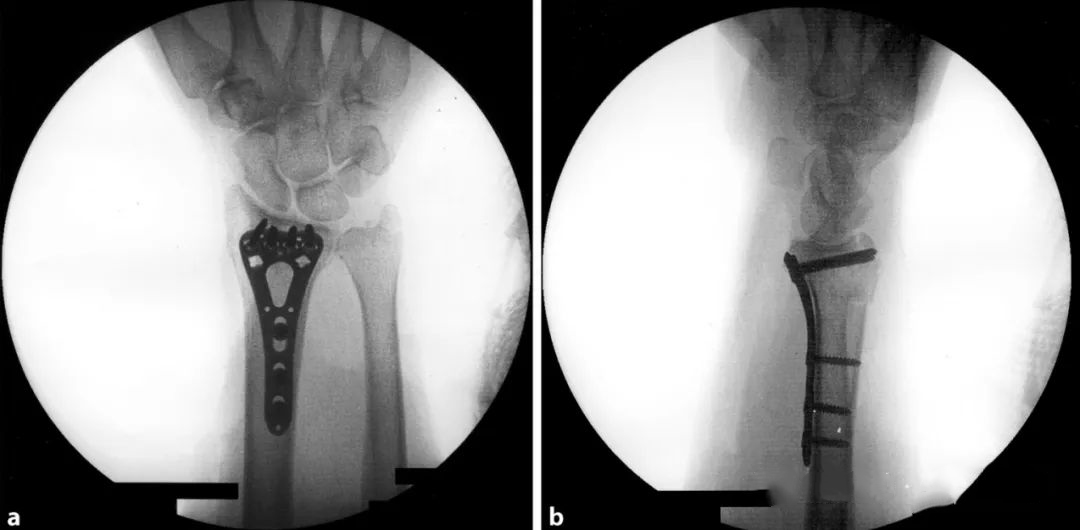

4.Внутренняя фиксация и рентгеноскопическая оценка

В настоящее время для оценки репозиции и положения винта используется внутренняя фиксация ладонной анатомической фиксирующей пластиной.Запястье приподнимается, чтобы компенсировать ладонный наклон и локтевую девиацию и избежать перекрытия суставных поверхностей: